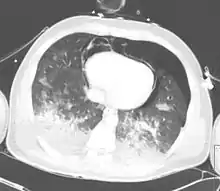

| A CT scan showing a pulmonary contusion (red arrow) accompanied by a rib fracture (purple arrow) | |

Computed tomography

Computed tomography (CT scanning) is a more sensitive test for pulmonary contusion,[6][33] and it can identify abdominal, chest, or other injuries that accompany the contusion.[38] In one study, chest X-ray detected pulmonary contusions in 16.3% of people with serious blunt trauma, while CT detected them in 31.2% of the same people.[45] Unlike X-ray, CT scanning can detect the contusion almost immediately after the injury.[43] However, in both X-ray and CT a contusion may become more visible over the first 24–48 hours after trauma as bleeding and edema into lung tissues progress.[46] CT scanning also helps determine the size of a contusion, which is useful in determining whether a patient needs mechanical ventilation; a larger volume of contused lung on CT scan is associated with an increased likelihood that ventilation will be needed.[43] CT scans also help differentiate between contusion and pulmonary hematoma, which may be difficult to tell apart otherwise.[47] However, pulmonary contusions that are visible on CT but not chest X-ray are usually not severe enough to affect outcome or treatment.[37]